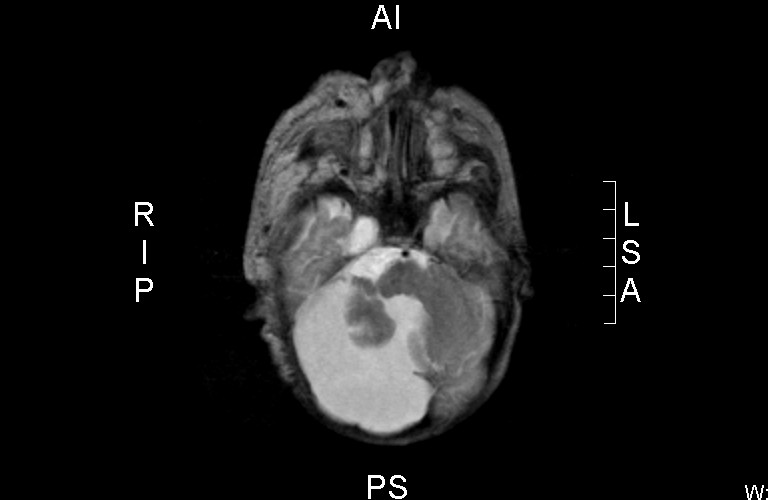

![Dandy-Walker malformatie (click on photo to enlarge) [source: www.huidziekten.nl] Dandy-Walker malformatie](../../../images/Dandy-Walker-malformatie-1z.jpg) |

Dandy-Walker malformatie |

MRI:

Beeld van hemangioom

in de cutis rechts parietaal en frontaal, doorlopend in de rechter orbita.

Hypoplasie van de vermis en de rechter cerebellum hemisfeer met wat wijde

achterste schedelgroeve, gevuld met liquor - beeld passend bij een

Dandy-Walker malformatie.